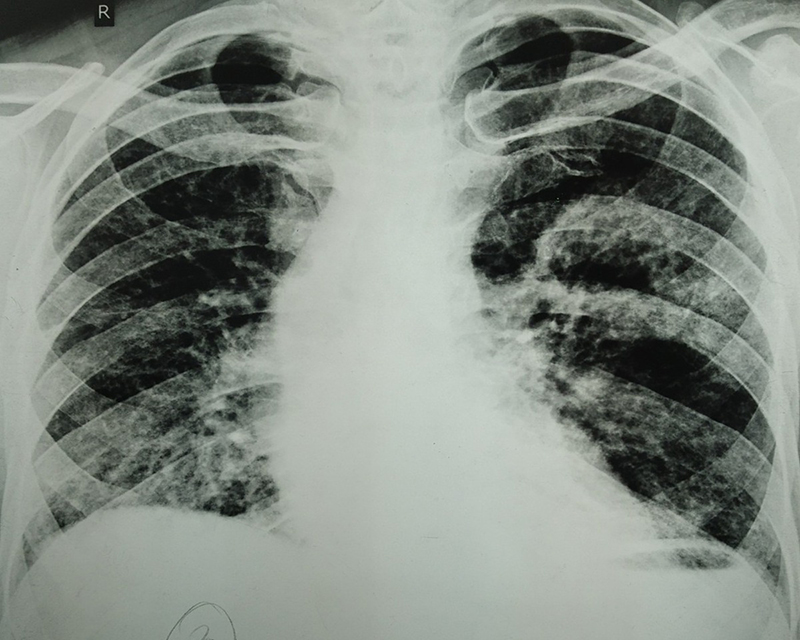

Figure 2

Figure 2. Enlargement and thickening of cavity at month 4 after ATT initiation.